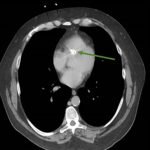

Endovascular coil embolization continues to become a more frequent modality of addressing hemorrhage and bleeding in patients. Migration refers to the coil unraveling or moving from the original embolization site. Migration of a coil is a known complication which can lead to serious consequences based on where the coil migrates. Despite increasing efforts to improve safety and technique, the risk of migration remains. We present a case of an embolization coil that migrated to the right ventricle, which was incidentally found roughly 2 months after undergoing an interventional radiology procedure for gastric variceal bleeding. The patient presented to the emergency department with dyspnea and abdominal pain. Unique images were obtained during his visit and in subsequent follow-up. As use of vascular embolization coils continues to become more commonplace, understanding the risks and complications of these procedures remains an important aspect of providing care for patients once they have left the interventional radiology suite. Coil migration should be a differential to consider in patients who present to the emergency department with signs or symptoms of arrhythmia or pulmonary embolism who have undergone a coil embolization procedure.